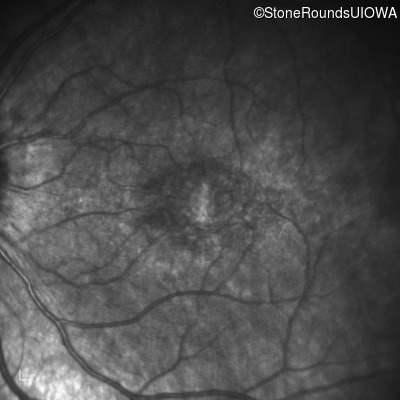

Infrared Fundus Photograph - Right - 20/80 -1

Exemplar